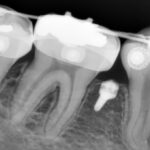

교정치료의 필요여부를 상담 후 보다 정확한 진단을 위해 치아의 모형채득, 구강내 구외 사진촬영, 전체 치아 및 안면 뼈를 볼수 있는 파노라마와 두경부 엑스레이 촬영 및 분석을 통해 치료가 시작됩니다. 총 치료 기간은 환자의 상태에 따라 6개월에서 3년 정도 걸리는 것이 일반적이며 치료 진행하는 동안 평균적으로 한달에 한번 정도 병원에 내원하게 됩니다. 장치 제거후에도 지속적인 유지 및 관리가 필요합니다.